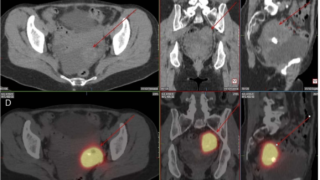

内服中はTRAbも陽性となるためバセドウ病と誤診しないことが重要。

全く症状がない場合に偶発的に検査で見つかった場合はバセドウ病と誤診され、抗甲状腺薬による治療が開始される恐れがあります。致死的な副作用を起こすこともあるので、そうなる前にサプリの接種歴についてしっかり問診をすることが大事。